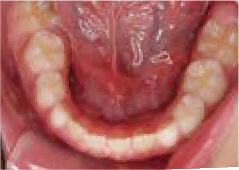

でこぼこ

でこぼこでも大丈夫。抜かずに、あごから育てる矯正治療

Jさん (矯正開始時:8歳)

Before

After

歯がガタガタに並んでいて、前歯の真ん中の位置が少し左にずれていました。

奥歯が生えるためのスペースが足りず、永久歯が生えて来られない状況が確認できました。

また、飲み込むとき下くちびるに力が入ってしまうクセが見られ、お顔全体の成長が遅れている様子が確認できました。

治療を終えて

歯がきれいに生えるためのスペースをしっかり確保することができ、歯並びを乱していたお口のクセも改善されたため、奥歯が生えるスペースを確保することができました。

しっかり噛めるかみ合わせを作ることが、将来の健康につながるので「よく噛む」練習も続けてもらっています。

主訴・治療内容 歯がガタガタになってきたことに悩み、無料相談に来院されました。

治療期間 3年

費用 462,000円(税込)